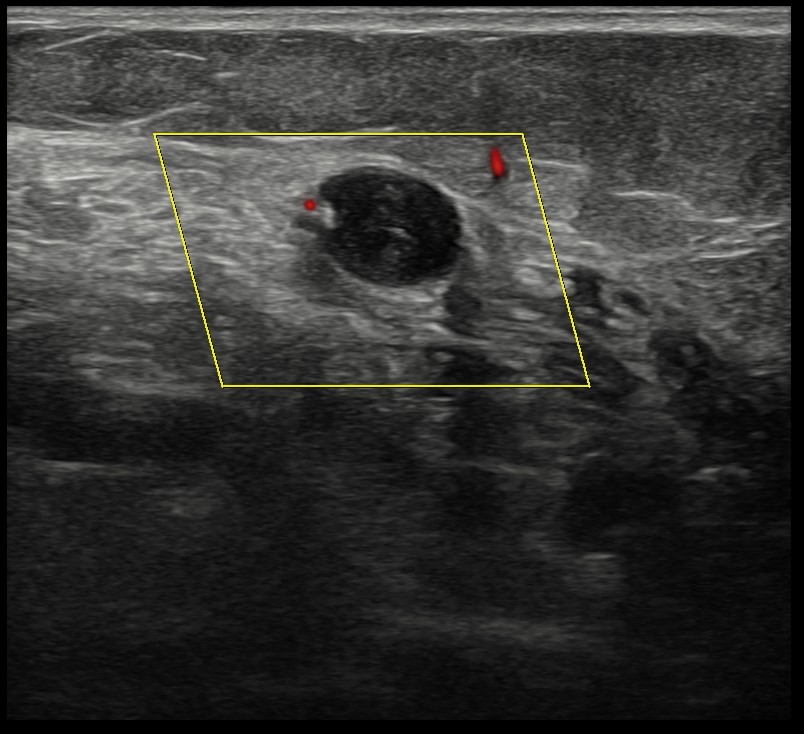

Mujer de 71 años que acude al Centro de Salud por dolor en la región superior de la pantorrilla izquierda. Refiere cuadro de lumbalgia en tratamiento analgésico con mejoría progresiva hasta seis días antes, cuando el dolor comenzó a irradiarse al miembro inferior izquierdo, focalizándose en la pantorrilla. Describe dificultad para la deambulación, sin alivio en reposo, y percepción de hinchazón y frialdad de la extremidad. Niega disnea, dolor torácico u otros síntomas sistémicos.Hallazgos ecográficos

Sistema venoso profundo no compresible en toda la pantorrilla izquierda, con material ecogénico intraluminal y ausencia de flujo en Doppler, hallazgos compatibles con TVP distal. Edema subcutáneo en región gemelar presente.Pruebas complementarias

Ante la sospecha diagnóstica deriva al Servicio de Urgencias Hospitalarias para confirmación diagnóstica mediante ecografía Doppler venosa y estudio analítico (D-dímero positivo).Juicio clínico, diagnóstico diferencial, concordancia con el hospital (en su caso)

Se confirma el diagnóstico de trombosis venosa profunda (TVP) frente a arteriopatía periférica o quiste de Baker, patologías que planteaban otras alternativas terapéuticas.Tratamiento, planes de actuación